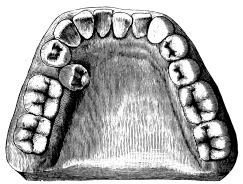

a  b  c  d

Fig. 21.

(a) Normal upper first permanent molar.

(b) Oblique rooted upper first permanent molar.

(c) Normal upper second permanent molar.

(d) Oblique rooted second permanent molar.

There is an abnormality of the upper molars which may with advantage be mentioned here. In this deformity the posterior buccal root is situated in a plane much internal to the anterior—in other words, it is an exaggeration of the normal arrangement. Such teeth have been termed by Mr. Booth Pearsall “oblique rooted” (fig. 21). The abnormality is met with most frequently in the third molar, sometimes in the second, rarely in the first. The difficulty encountered in extracting these teeth is{27} that the outer blade of the forceps tends to slip round. Oblique-rooted teeth can at times be diagnosed by noting an undue prominence of the alveolus over the anterior buccal root, and are best removed with forceps similar to that shown in fig. 20.